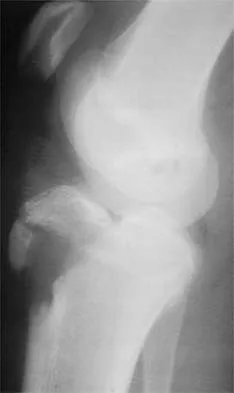

Figure 35 shows the lateral radiograph of a 15-year-old basketball player who felt a dramatic pop in his knee when landing after a lay-up. The patient reports that he cannot bear weight on the injured extremity. Management should consist of

Explanation